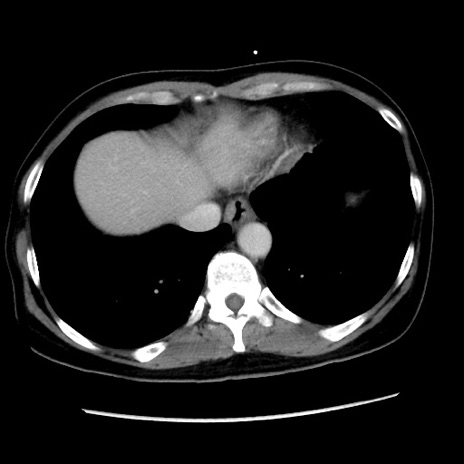

症例10(横断像)

【症例】 50歳代女性

【主訴】 腹痛

【現病歴】前日生レバーを食べた。今朝に排便あり。 昼前に突然発症の腹痛を生じ、当院救急外来を受診した。

【既往歴】 子宮筋腫にてで子宮全摘後

【身体所見】 意識清明、腹部:平坦、軟、下腹部やや左を中心に圧痛・反跳痛あり、筋性防御あり

【データ】WBC 7800、CRP 0.07